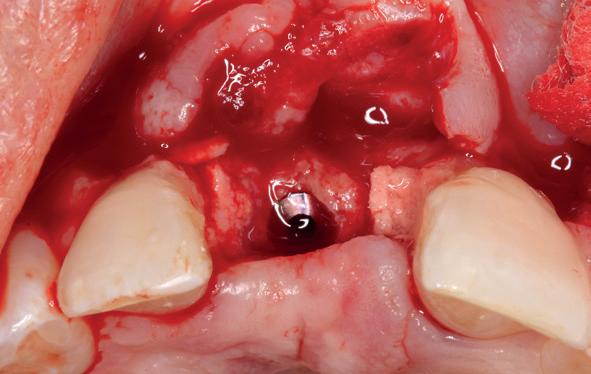

5. Implantaten geplaatst op geleide van een boorsjabloon; botopbouw met sinuslift volgens de GBR-techniek en Caldwell Luc methode; materialen: Oragraft & BioOss, Ossix membr, hyaluronzuur. In de BK is gekozen voor Bego implantaten (Bego SC en RSX 3,75x 11,5 & 13mm).

6. In het front zijn Bego 3,25mm

Tijdens de chirurgische behandeling worden na het afschuiven van de flap de posities bepaald van de implantaten met de boorsjabloon. In de bovenkaak worden 7 implantaten geplaatst en in de onderkaak 8

implantaten geplaatst terwijl in de zijdelingse delen voor een bredere diameter (3,75 & 4,1) is gekozen, met lengte 8,5 en 10mm.

(zie foto’s chirurgie en OPT’s). Gekozen is voor Bego SC & RSX Pro van een relatief smalle diameter (3,253,75). Alleen in de molaarstreek valt de keuze op een 4,1 mm in diameter. De lengte varieert tussen 8,5 en 13 mm afhankelijk van de ligging van de nervus alveolaris inferior en het foramen mentale als de neusbodem en de sinusholte. De keuze van de diameter wordt mede bepaald door de breedte van de processus ondanks de uit te voeren laterale botopbouw. Indien mogelijk gaat de voorkeur uit naar het plaatsen van implantaten in autoloog en daarmee vitaal bot.